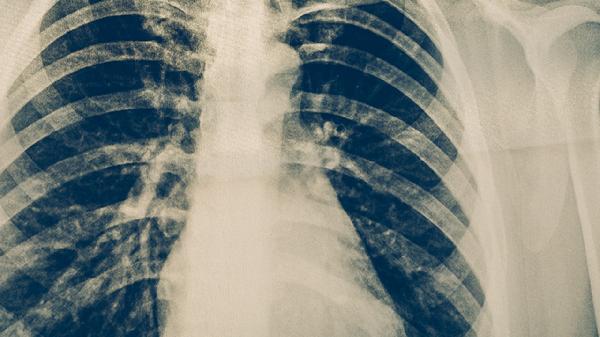

約三分之一的肺結(jié)核患者會出現(xiàn)咯血癥狀,表現(xiàn)為痰中帶血絲或少量鮮血。嚴(yán)重者可發(fā)生大咯血,這種情況多與肺部血管受到結(jié)核病灶侵蝕有關(guān)。咯血時患者可能同時感到咽喉部有血腥味,需要警惕窒息風(fēng)險。

肺結(jié)核引起的胸痛多為鈍痛或隱痛,位置較固定,常在深呼吸或咳嗽時加重。這種胸痛與胸膜受到炎癥刺激有關(guān),當(dāng)病變累及胸膜時可出現(xiàn)胸膜摩擦感。部分患者可能誤以為是心臟疾病或肌肉拉傷導(dǎo)致的疼痛。